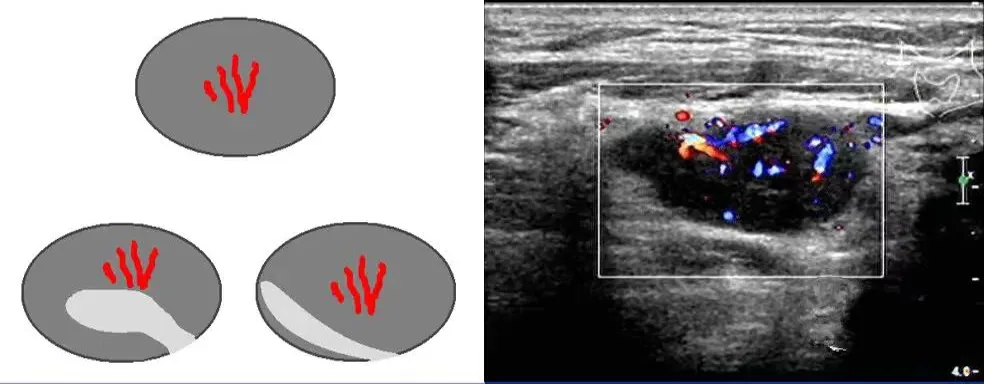

淋巴门型

血流信号沿着高回声的淋巴门分布,或从淋巴门血管主干放射状发出,该血流可位于淋巴结中央或边缘,多见于良性淋巴结及淋巴瘤。

中央型

血流信号位于淋巴结中央,经多切面扫查均显示该血流信号不是来自淋巴结门部,尤其是紊乱的中央型血管见于恶性淋巴结。

周边型

血流信号位于淋巴结周边部,而淋巴门无血流信号,多见于淋巴结转移癌和淋巴瘤。

混合型

同时显示上述三种血流类型的两种或三种,可见于恶性淋巴结和结核性淋巴结。